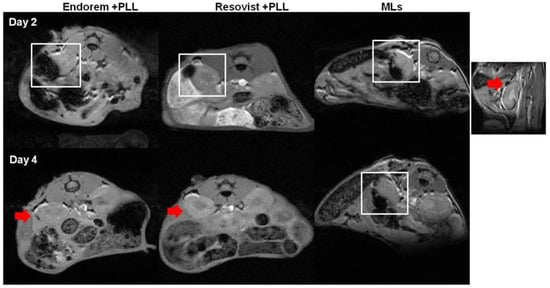

We assessed the feasibility of monitoring islets transplanted in the sub-capsular space of kidneys in healthy mice longitudinally, by using in vivo MR imaging. We implanted 200 PIs, labeled with Endorem (+PLL), Resovist (+PLL), or MLs under the left kidney capsule. Figure 6 indicates MRI performed at the different time points, indicating a marked decrease in the signal intensity (white square in Figure 6) on T2-weighted MR images. PIs labeled with MLs showed a hypointense signal until day four, whereas PIs labeled with Endorem or Resovist (+PLL) did not show any hypointense signals by day four. The higher MRI sensitivity of MLs can be explained by intracellular aggregation caused after partial degradation of the outer lipid layer in the lysosomal environment [31,32].

Figure 6. MR imaging of transplanted islets: MR imaging was performed to detect the labeled islets in vivo. The hypointense sub-capsular region (highlighted by white square) indicates PIs labeled with Endorem + PLL and Resovist + PLL. Endorem or Resovist + PLL-labeled islets were not detectable on day four in the sub-capsular region (red arrows), whereas PIs labeled with MLs were detectable until day four (indicated by white square). The right corner image indicates a prominent black spot (red arrow) seen on the sub-capsular region after transplantation of PIs labeled with MLs.